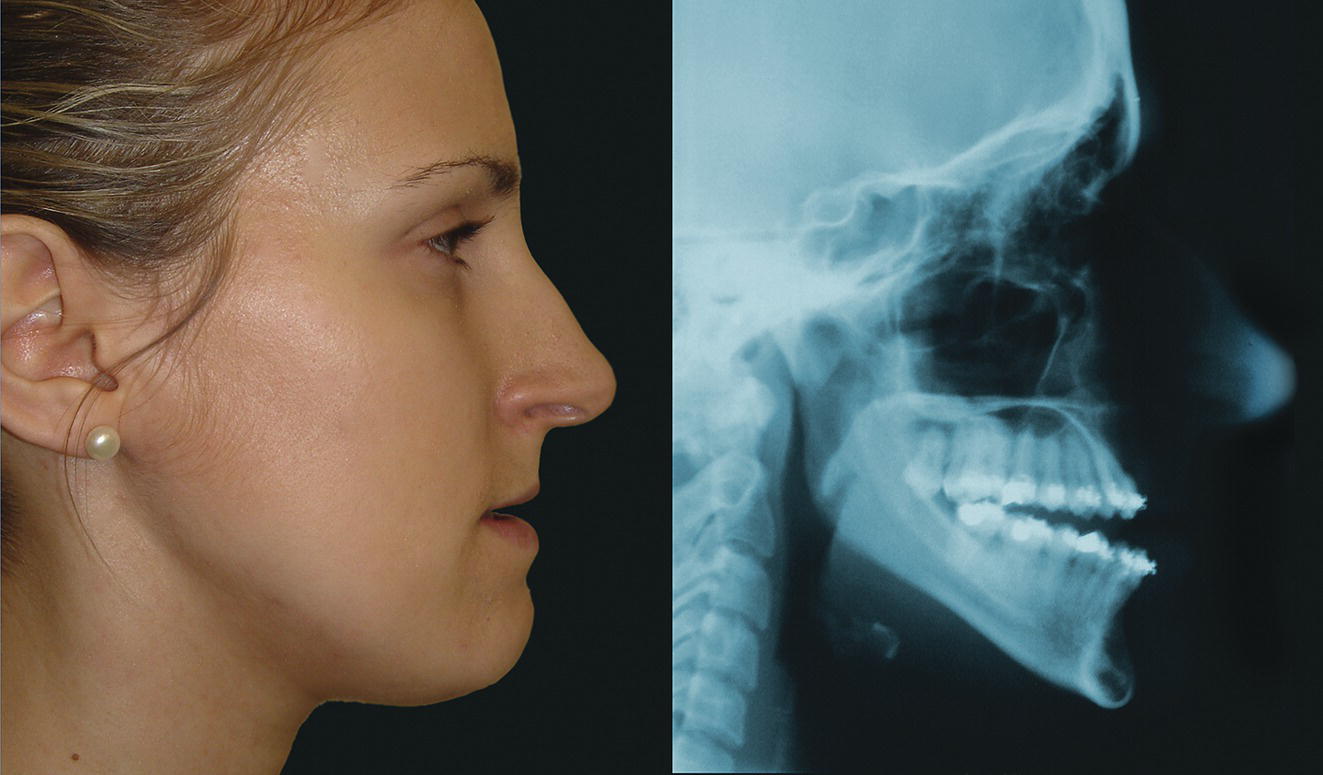

Facial type: profile view (norma lateralis)

Sagittal facial profile contour

Vertical facial profile form

Vertical facial growth pattern and hyperdivergent facial type (Figure 8.15)